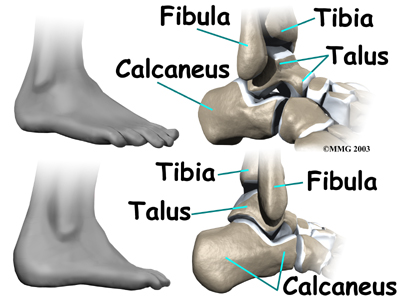

Ankle Impingement Problems

The ankle joint is formed where the bones of the lower leg, the tibia and the fibula, connect above the anklebone, called the talus. The tibia is the main bone of the lower leg. The fibula is the small, thin bone along the outer edge of the tibia.